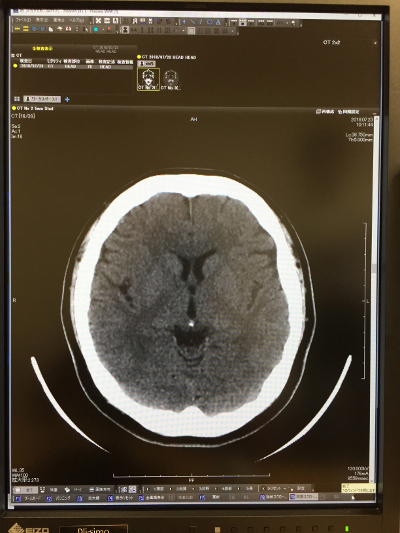

CT<頭部>